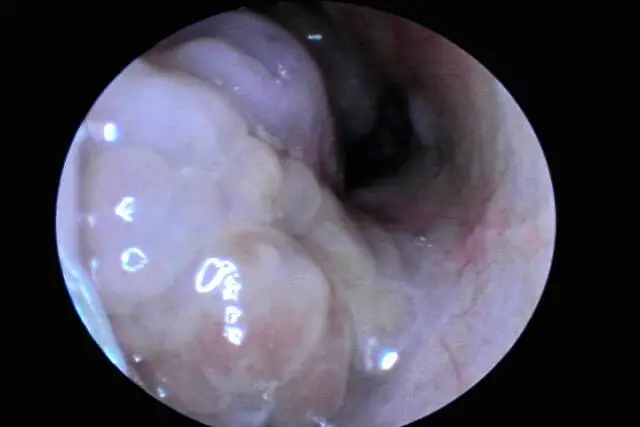

鼻息肉

鼻息肉作為一種常見病癥,其主要癥狀為鼻塞、呼吸不暢以及嗅覺失靈。病癥隨著息肉數(shù)量增加而漸趨嚴(yán)重,預(yù)防措施至關(guān)重要。